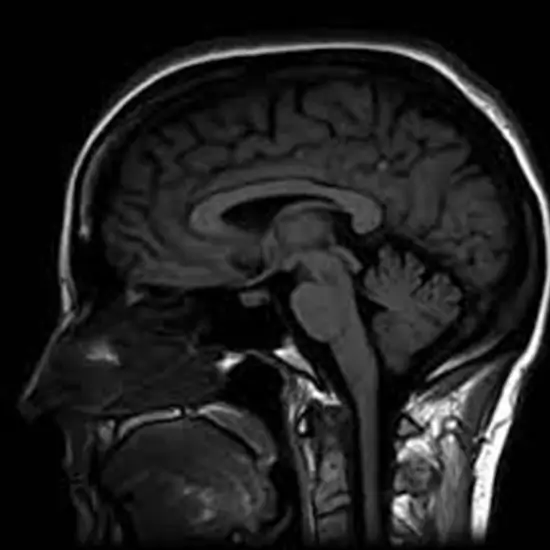

MRI Brain With Contrast

MRI Brain with Contrast is a contrast-enhanced MRI scan. Adding contrast allows the radiologist to detect even the smallest tumour and provides information about the tumour's precise location. The radiologist can better interpret an MRI contrast scan because they have more clarity and produce higher-quality images.